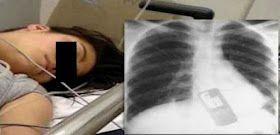

نجح فريق من الأطباء البرازيليين في إنقاذ شابة من موت محقق، بعدما أخرجوا هاتفا محمولا من معدتها كانت قد ابتلعته خوفا من اكتشاف خيانتها من طرف صديقها.

و نقلت وسائل إعلام عالمية، أن الأطباء أجروا عملية جراحية للفتاة التي تبلغ 19 سنة من عمرها، و ذلك بعدما ابتلعت هاتفها المحمول و ذلك مخافة أن يقرأ صديقها رسائلها الخاصة، بعدما شك في كونها تتكلم مع شاب آخر غيره.

و أضافت المصادر ذاتها، أنه بعدما طالب الشاب الفتاة بإعطائه الهاتف لكي يطلع على ما يحتويه من رسائل، رفضت الشابة ذلك و ابتلعته، مما تسبب لها بمشاكل صحية خطيرة نُقلت على إثره إلى المستشفى حيث أجريت لها عملية جراحية كللت بالنجاح.